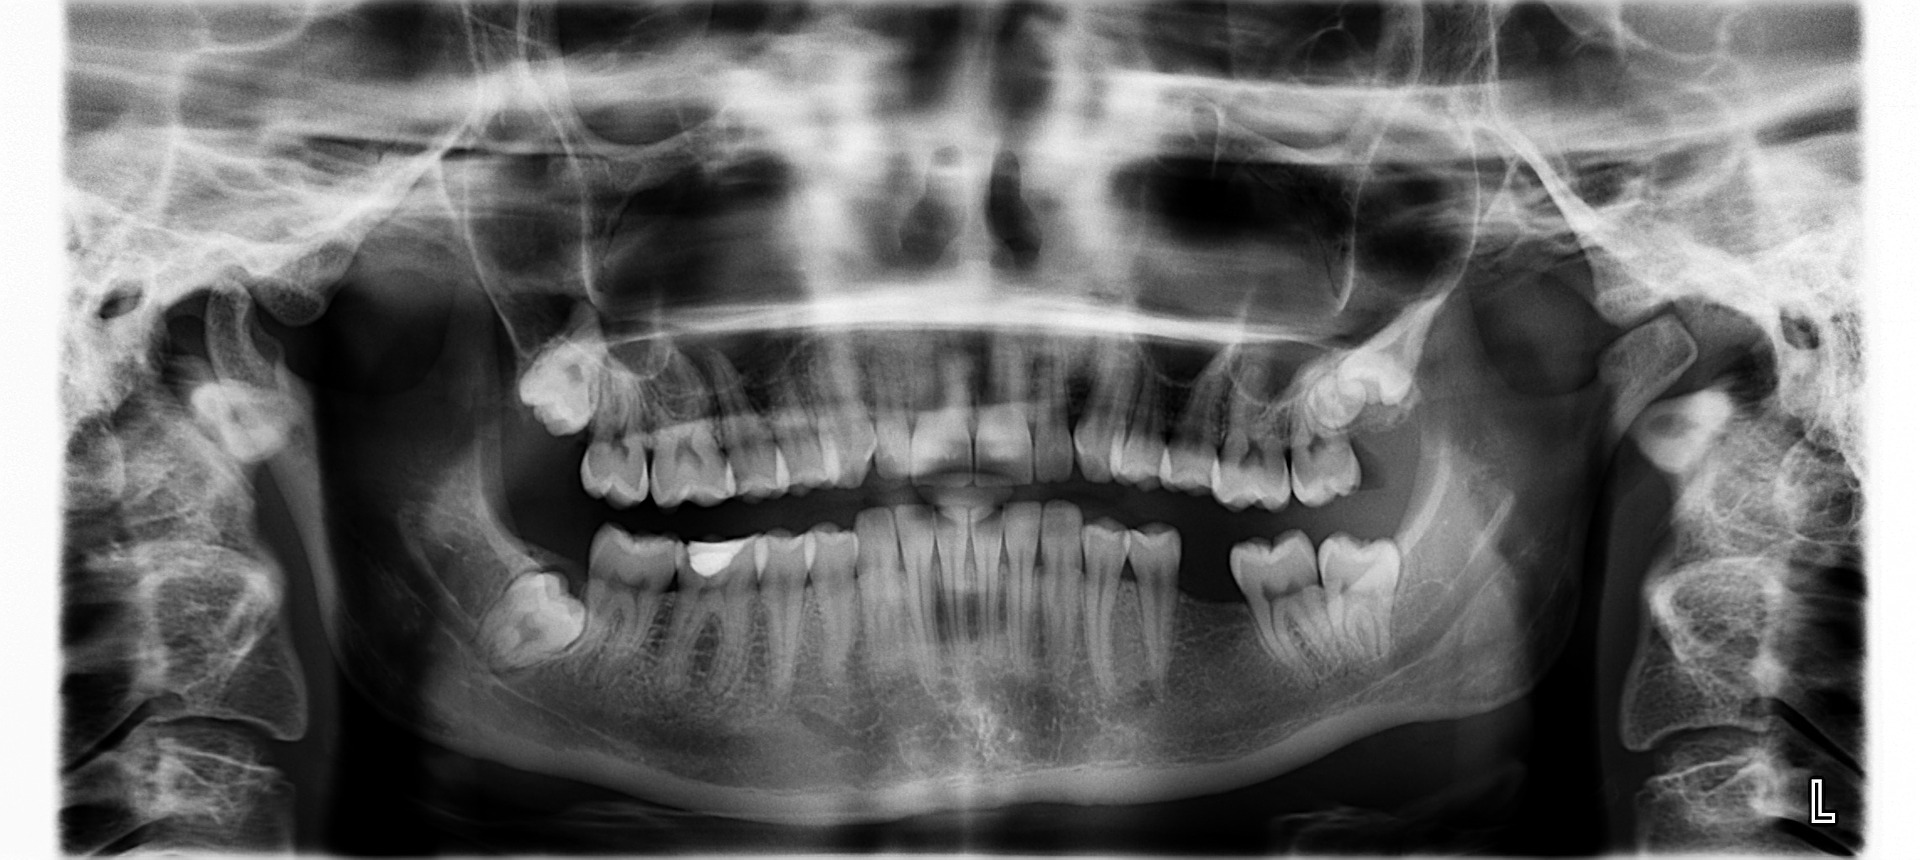

Röntgentutkimus

Leukaperät kuvataan röntgenillä ja määritetään luukudoksen kunto ja anatomia.